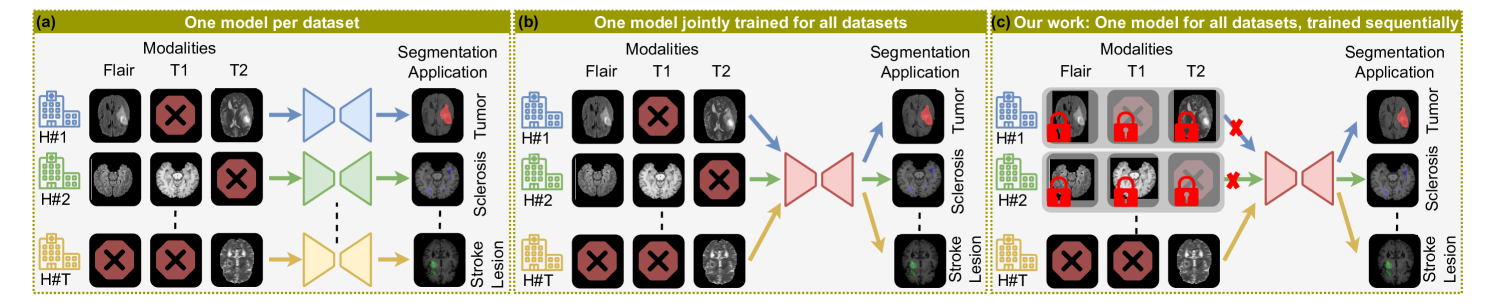

Magnetic Resonance Imaging (MRI)-based brain lesion segmentation is crucial in neurology for analysis, surgery planning, and functional imaging. However, real-world clinical applications face challenges due to patient, scanner, and pathology variability. Traditionally, UNet-based models are trained for specific pathologies with fixed modalities, limiting flexibility. This often requires training separate models for different modality-pathology combinations (Fig. 1a), which is resource-intensive and less flexible. In contrast, clinicians adapt to different diseases and modalities. Likewise, a single model learning from diverse datasets can enhance performance by leveraging pathology relationships, especially for small datasets. Recent studies [Xu et al.(2024)Xu, Moffat, Seale, Liang, Wagner, Whitehouse, Menon, Newcombe, Voets, Banerjee, et al., Wagner et al.(2024)Wagner, Xu, Saha, Liang, Whitehouse, Menon, Voets, Noble, and Kamnitsas] train a single UNet on multiple datasets with variable modalities (Fig. 1b). While this enables multi-dataset segmentation, it requires all datasets to be available simultaneously. Moreover, performance drops if test data differ in hospital, disease type, or lesion size.

This work addresses variable modality MRI segmentation, where datasets arrive sequentially rather than all at once (Fig. 1c). Continual Learning (CL) enables a single model to learn new datasets while retaining past knowledge [McCloskey and Cohen(1989), Ratcliff(1990)]. Naively updating a UNet-based model disrupts previous weights, causing catastrophic forgetting. CL prevents this by using strategies such as storing past data, limiting weight changes, or allocating parameters per dataset. CL is gaining interest in medical image analysis [Kumari et al.(2024)Kumari, Reisenbüchler, Luttner, Schaadt, Feuerhake, and Merhof, Kumari et al.(2023)Kumari, Chauhan, Bozorgpour, Azad, and Merhof] and more specifically also in studies for brain MRI segmentation under domain shifts [Karani et al.(2018)Karani, Chaitanya, Baumgartner, and Konukoglu, van Garderen et al.(2019)van Garderen, van der Voort, Incekara, Smits, and Klein, Baweja et al.(2018)Baweja, Glocker, and Kamnitsas]. However, modality variability remains unexplored. We improve upon [Xu et al.(2024)Xu, Moffat, Seale, Liang, Wagner, Whitehouse, Menon, Newcombe, Voets, Banerjee, et al.] by enabling CL in 3D-UNet without requiring all datasets to be available simultaneously. Our buffer-free approach learns from diverse brain MRI datasets from different hospitals and pathologies. It combines dual-distillation-based regularization with soft parameter isolation for domain adaptation. The dual-distillation method transfers knowledge from the previous model at the feature and response levels to the new model trained on incoming data. Additionally, we integrate mixture-of-experts (MoE) [Shazeer et al.(2017)Shazeer, Mirhoseini, Maziarz, Davis, Le, Hinton, and Dean] within each encoder and decoder layer of UNet to minimize interference between datasets. These experts are activated differently for each data distribution using a domain token, a binary vector encoding modality and pathology information. This targeted activation mechanism helps the model retain knowledge from past datasets more effectively. We summarize our contributions as follows: ❶ To the best of our knowledge, this is the first study exploring CL for brain MRI segmentation under domain shifts, including heterogeneous modalities, pathologies, and acquisition centers. ❷ We introduce a novel domain-conditioned MoE in UNet, incorporating modality and pathology information for 3D segmentation. ❸ Our dual-distillation and MoE-based CL strategy outperforms existing buffer-free CL methods.